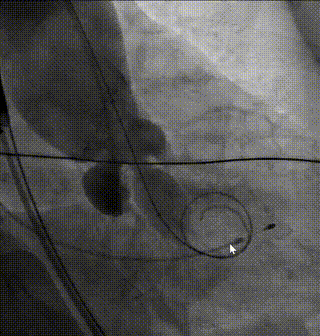

造影评估深度1

造影评估深度2

完全释放